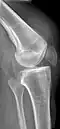

| An x-ray demonstrating quadriceps tendon rupture. Note the abnormal angle of the patella and soft-tissue swelling marked by the arrow. | |

Quadriceps tendon rupture in plain X-ray -